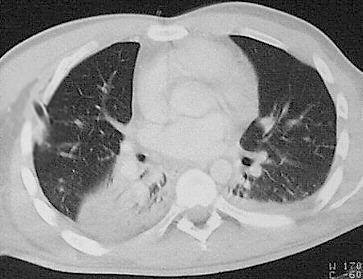

Metastasen

Eine pulmonale Metastasierung ist häufig insbesondere bei Colon-, Pankreas-, Mamma-, Nierenzell-, Prostatakarzinomen und dem malignen Melanom. Lungenmetastasen stellen sich in der Computertomographie als meist multiple, weichteildichte Rundherde dar, die ab einer Grösse von ca. 2 mm computertomographisch nachweisbar sind. Sie treten hydrostatisch bedingt dorsobasal häufiger auf.